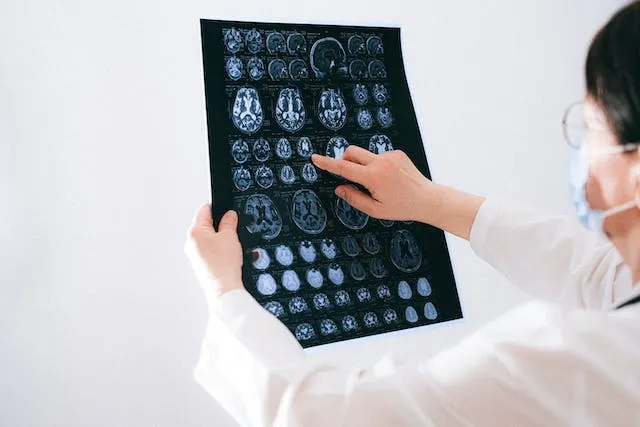

起初,TF因為頭疼和癲癇發作的症狀就醫,醫生也很常規的對他進行一些腦部檢查,看看是不是有腦損傷,因為他的症狀符合腦部損傷所致。令人驚奇的是,通過對他的大腦進行核磁共振掃描和其他檢查,醫生髮現他患有重度腦水腫,這導致他的大腦皮層受到了嚴重的損傷。

由於當時科學技術條件有限,加之病情嚴重,醫生通過CT無法觀察到他完成的腦部結構,整個CT顯示他腦部只有大量液體組織,就像是整個頭顱內裝滿了水,如此奇怪的現象,直接讓醫生蒙圈了:接診看病這麼多年,頭一次見到沒有大腦,還能娶妻生子,長大到現在這個年齡,才走進醫務室的無腦人!